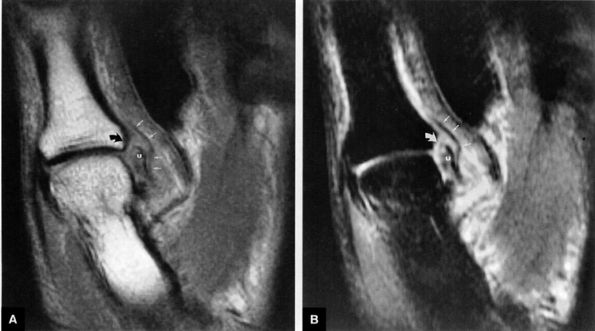

However, a fluid-filled gap interposed between the membranous scapholunate ligament and the cartilage or bones should be interpreted as a perforation or detachment. Such membranous scapholunate ligament perforations and detachments are more common with advancing age (similar to tears of the TFC central disc), and in isolation may not necessarily result in carpal instability or significant symptoms. The volar-most images demonstrate the volar scapholunate ligament, which courses obliquely and attaches to bone on either side of the ligament. Tears of the volar and radial aspects of the scapholunate ligament suspected in the coronal plane can be confirmed in the axial plane. After identifying a scapholunate ligament tear, the scapholunate interval is assessed for widening, reactive bone marrow changes on either side of the scapholunate articulation, and bony or cartilaginous avulsions at the site of tearing or detachment. In addition, in the setting of scapholunate ligament tears, associated patterns of carpal instability, such as dorsal intercalated segment instability (DISI) pattern, can be identified on corresponding sagittal images.

![]() |